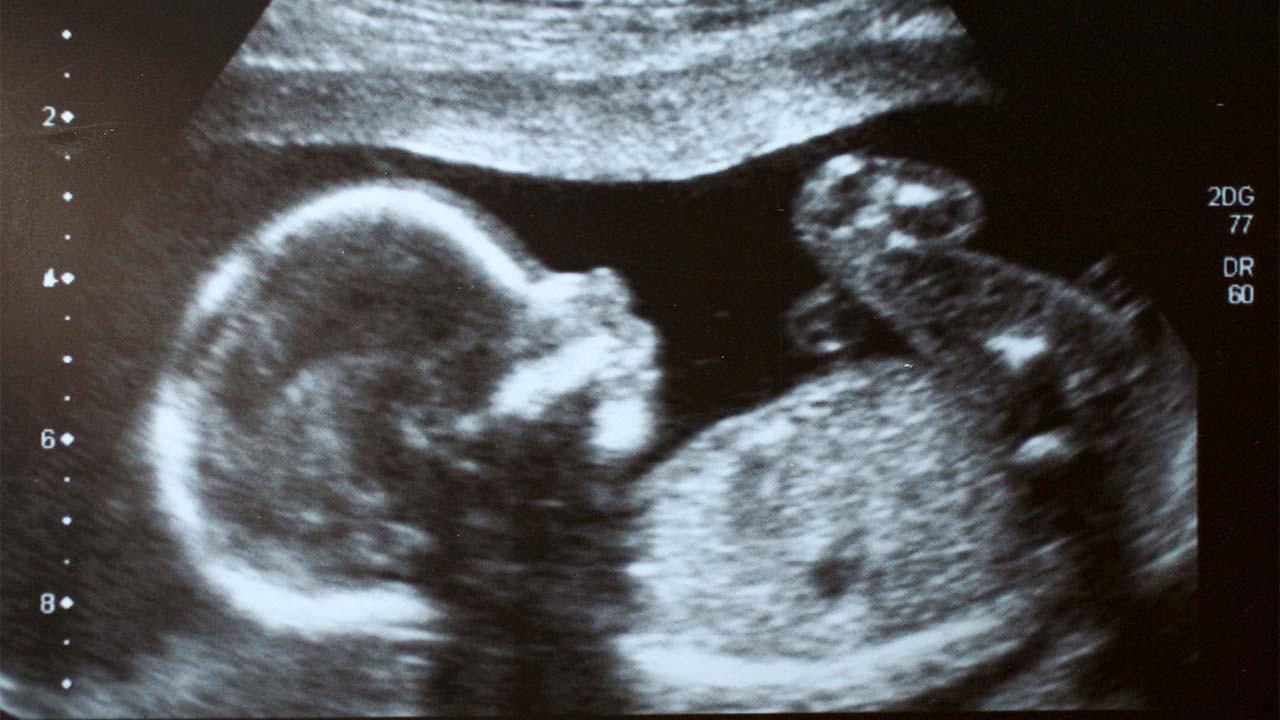

Before the baby was born, medical checks and ultrasound examinations of her mother had shown that the child had a large stomach.

It was then confirmed after her birth that she had a twin embryo inside her stomach.

The baby reportedly underwent ultrasound examinations and an X-ray before doctors removed two more formations from inside her stomach.